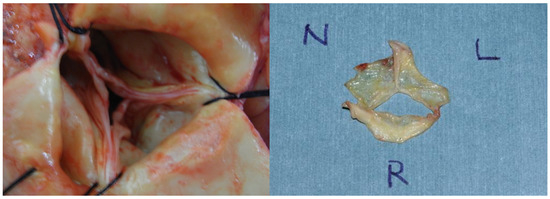

3.5. Intraoperative Pathological Findings Associated with Aortic Regurgitation

| Main reason of AR | ||||

| Prolapse | 2 | 1 | 1 | |

| Degenerative change | 5 | 1 | 4 | |

| Dilatation of annulus | 1 | 0 | 1 | |